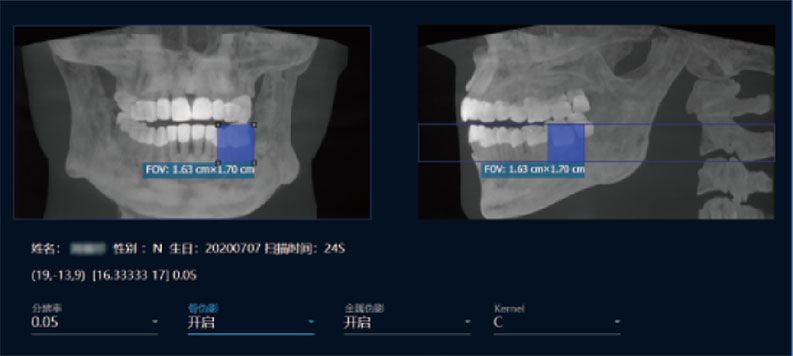

局部超清显示、 移动视野摄片

真人正侧位投影,实现CT成像区域无极可调

可根据临床需求任意调整成像区域大小实现局部超清三维显示